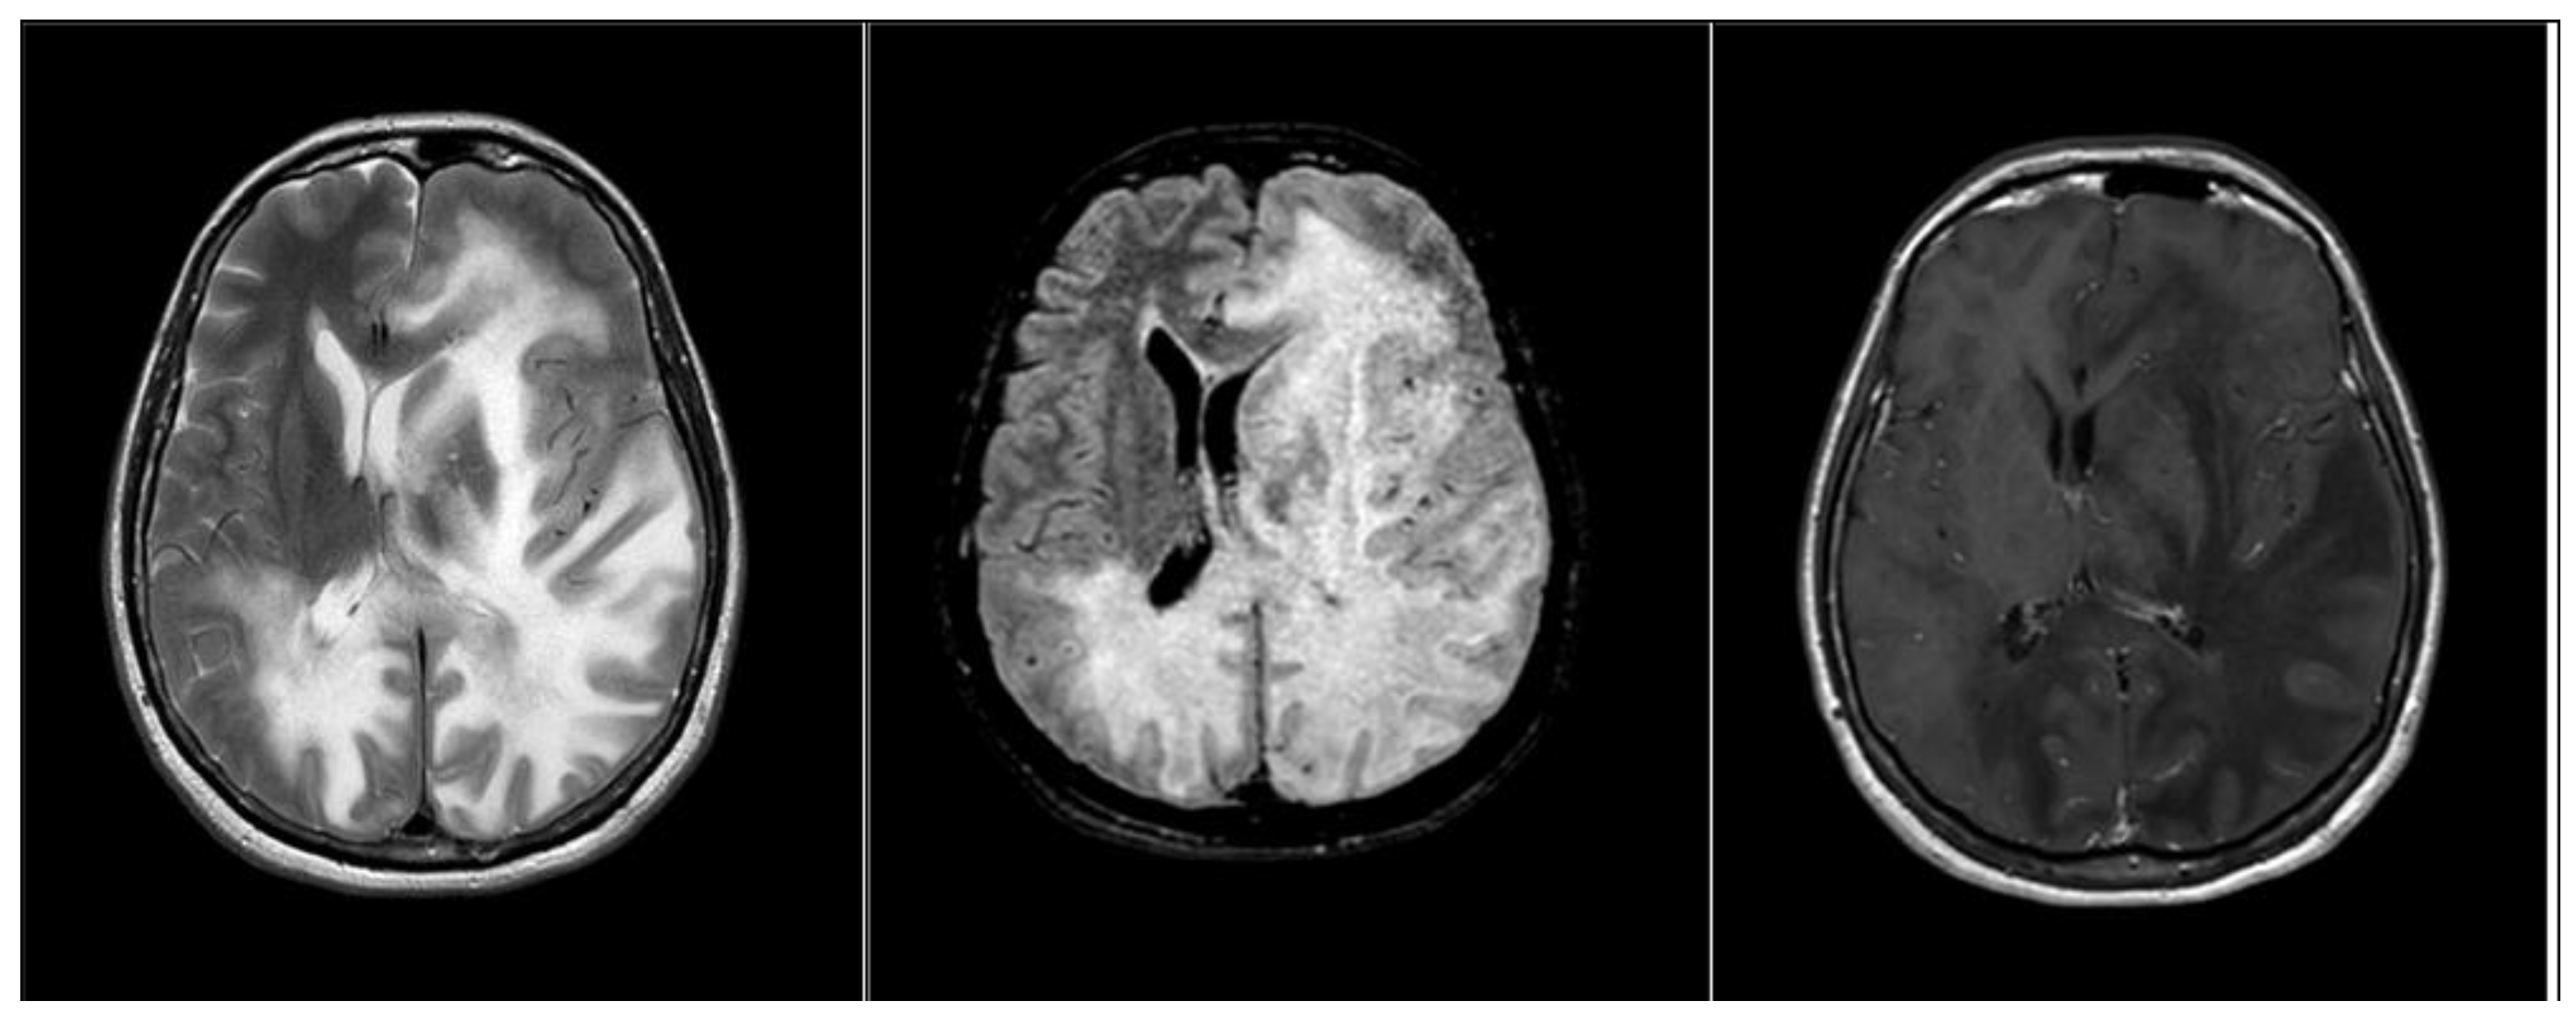

2. Case Presentation